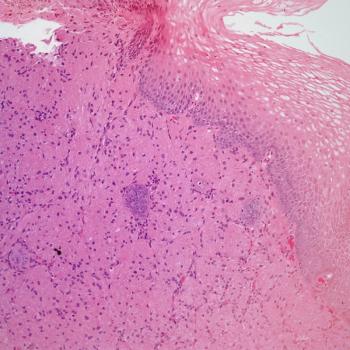

A 32-year-old man presents with a firm nodule in his arm. Resection of the nodule is performed. What is your diagnosis?